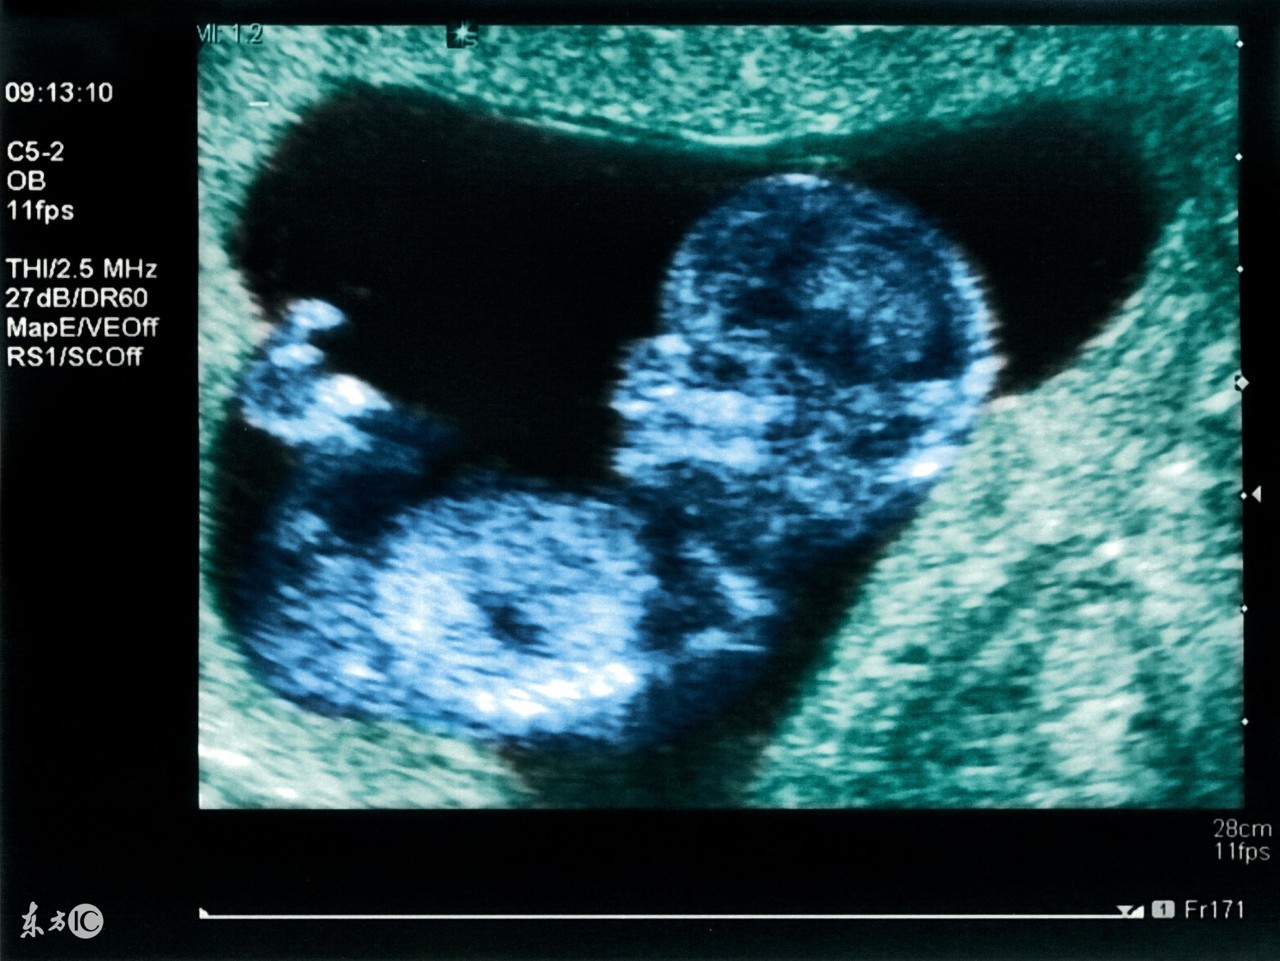

在妇产科方面,四维彩超能够对胎儿进行超声检查能立体显示胎儿的颜色、面、各器官的发育情况,甚至胎儿在母体里的状态也可以观察到;对胎儿畸形,如唇裂、腭裂、骨骼发育异常、血汗管畸形等能早期诊断。

四维彩超成像的较佳时间是22—28周,这段时期检查,因为胎儿较小,羊水适中,胎儿活动度大,体表也比较丰满,有利于胎儿四维超声成像和胎儿畸形筛查。